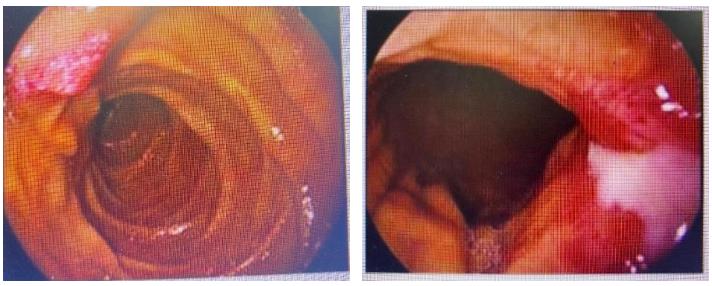

胃镜:贲门下方、胃体前壁、胃体小弯侧、胃体后壁见巨大溃疡性肿物,考虑胃癌并出血。

图2.胃镜